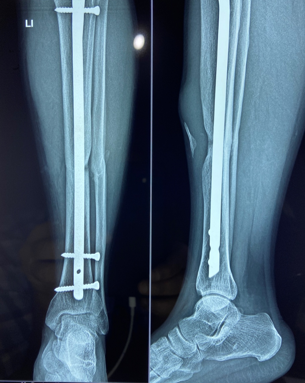

In a series of delayed union with internal fixation over 47 patients regardless of the fracture sites communition or inadequate fixation, had union in all patients including a case of infected nailing of femur. These patients had reported to Dr. S S Jha three to seven months after internal fixation at other centers. None of these patients were willing to submit themselves for further surgical intervention. Teriparatide 20mcg daily through subcutaneous route was started in all patients with adequate supplementation of vitamin D and calcium. Evident radiological bony union was perceptible after three months with clinical improvement in the initial presenting symptoms of the patients and the osseous consolidation was invariably observed radiologically within four to six months. It was only in six patients that Teriparatide was continuously used for one and half years for reasons of general debility, elderly age and osteoporosis. Radiographs of three difficult cases are being displayed from the series.

Case 1([Figure 1], [Figure 2], [Figure 3], [Figure 4], [Figure 5], [Figure 6], [Figure 7], [Figure 8], [Figure 9])

Case 2([Figure 10], [Figure 11])

- Case 1([Figure 1], [Figure 2], [Figure 3], [Figure 4], [Figure 5], [Figure 6], [Figure 7], [Figure 8], [Figure 9])

- Case 2([Figure 10], [Figure 11])